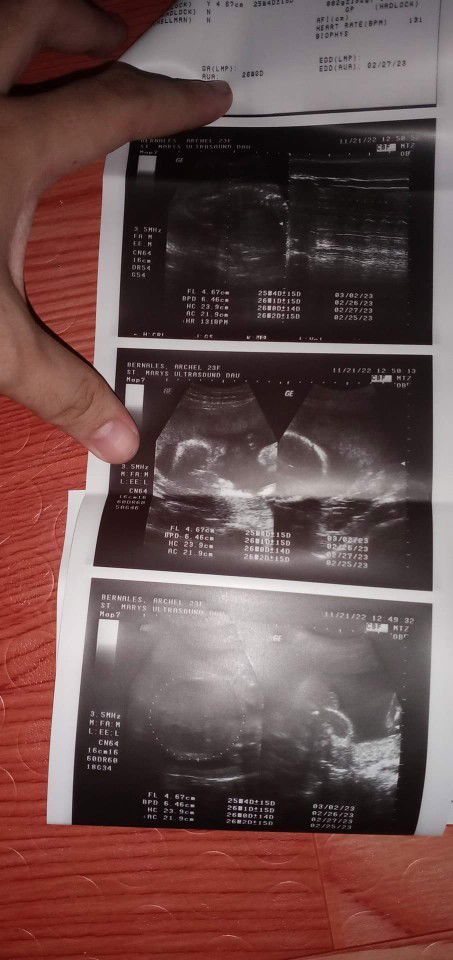

Baby girl po daw si baby, pero naka breech yung position nya. Pasimble po kaya nag kamali sila? Or tama? Kase dami po nag sasabi na lalaki si baby

Magbasa pasa akin my at 5 mos transverse lie baby girl, sabi nila baka nagkamali lalaki daw kasi majority sa side ng husband ko poro boys. 28 weeks repeat scan kasi nag spotting ako naka breech girl padin ang gender, sabi na naman nila di dw accurate kasi breech, at 35 weeks repeat scan na naman ayun cephalic na walang nag bago still baby girl, wag ma pressure sa sabi2 mi trust lang sa sonologist mo sasabihin naman nila if di sila sure sa gender if ever di nila makita i advise ka naman nila for repeat scan. goodluck my

First ultrasound ko mi ay breech position din si baby pero nalaman agad yung gender niya na baby girl siya at nagtugma po sa 2nd ultrasound ko which is nakacephalic position na siya. Marami rin nagsasabi sakin na baka daw po baby boy kasi sa shape ng tummy ko pero mas naniwala ako sa result ng ultrasound na baby girl.

Magbasa pasame sakin sis ..unang ultrasound ko 21 weeks frank breech sya at baby girl ..not sure pa si sonologist .. repeat ako ultrasound nung 28 weeks sa ibang oby.gyne naman yun nakapwesto ma sya at 100 % girl nga .. dami din nag sabi na boy sakin pero mas naniwala ako sa nag ultrasound .sakin kasi sila mas expert .